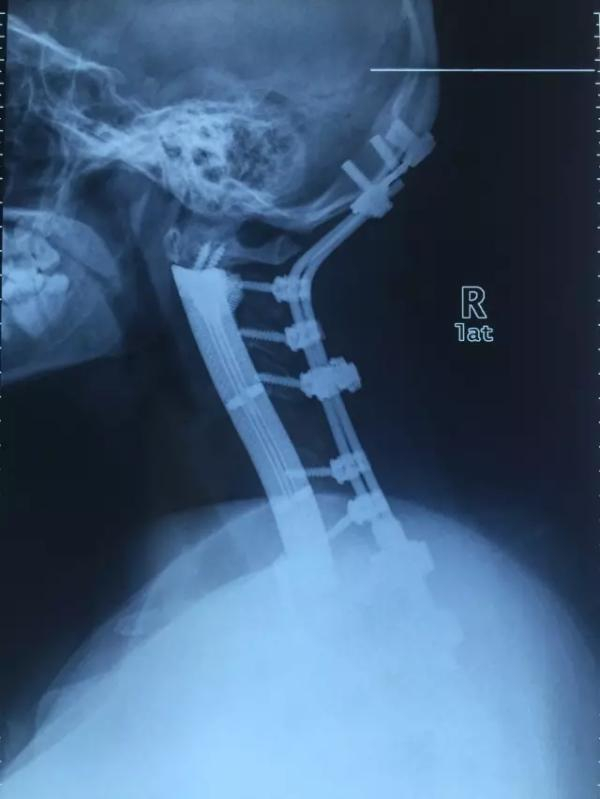

术后,在X光片里,小雯脑袋和身体之间的连接是前后两段金属。其中,作为主力支撑的3D钛合金假体14厘米长,有着可以察觉的曲度。

小雯术后的X光片

上海长征医院骨肿瘤外科的肖建如是这次手术的主刀。8月7日,在位于上海长征医院的办公室里,肖建如拿出小雯术后的X光照片,忍不住对澎湃新闻(www.thepaper.cn)说:“这个术后照片很漂亮。”